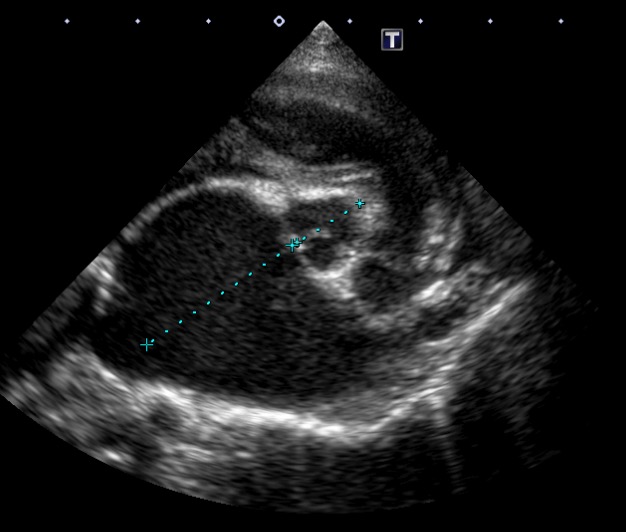

レントゲン検査において、心陰影の拡大(心肥大)が認められ、超音波検査において重度の僧帽弁閉鎖不全症と左心房の拡大が確認されました。

初診時の超音波検査 左心房の拡大

1年後の超音波検査 左心房の縮小